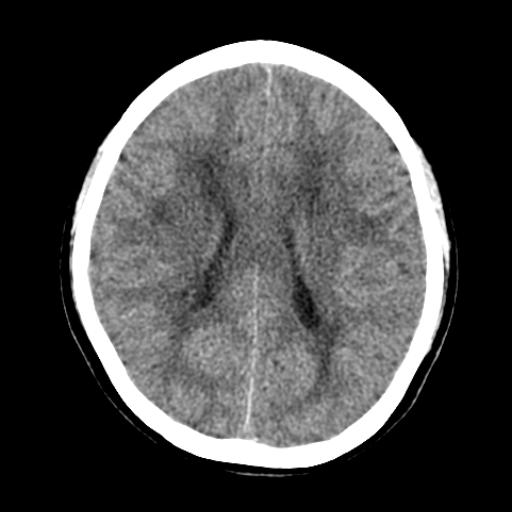

40f头晕十多天,右上肢麻木一天

脑白质变性或ms

脑白质脱髓鞘改变。

脑白质病;建议行mri检查。